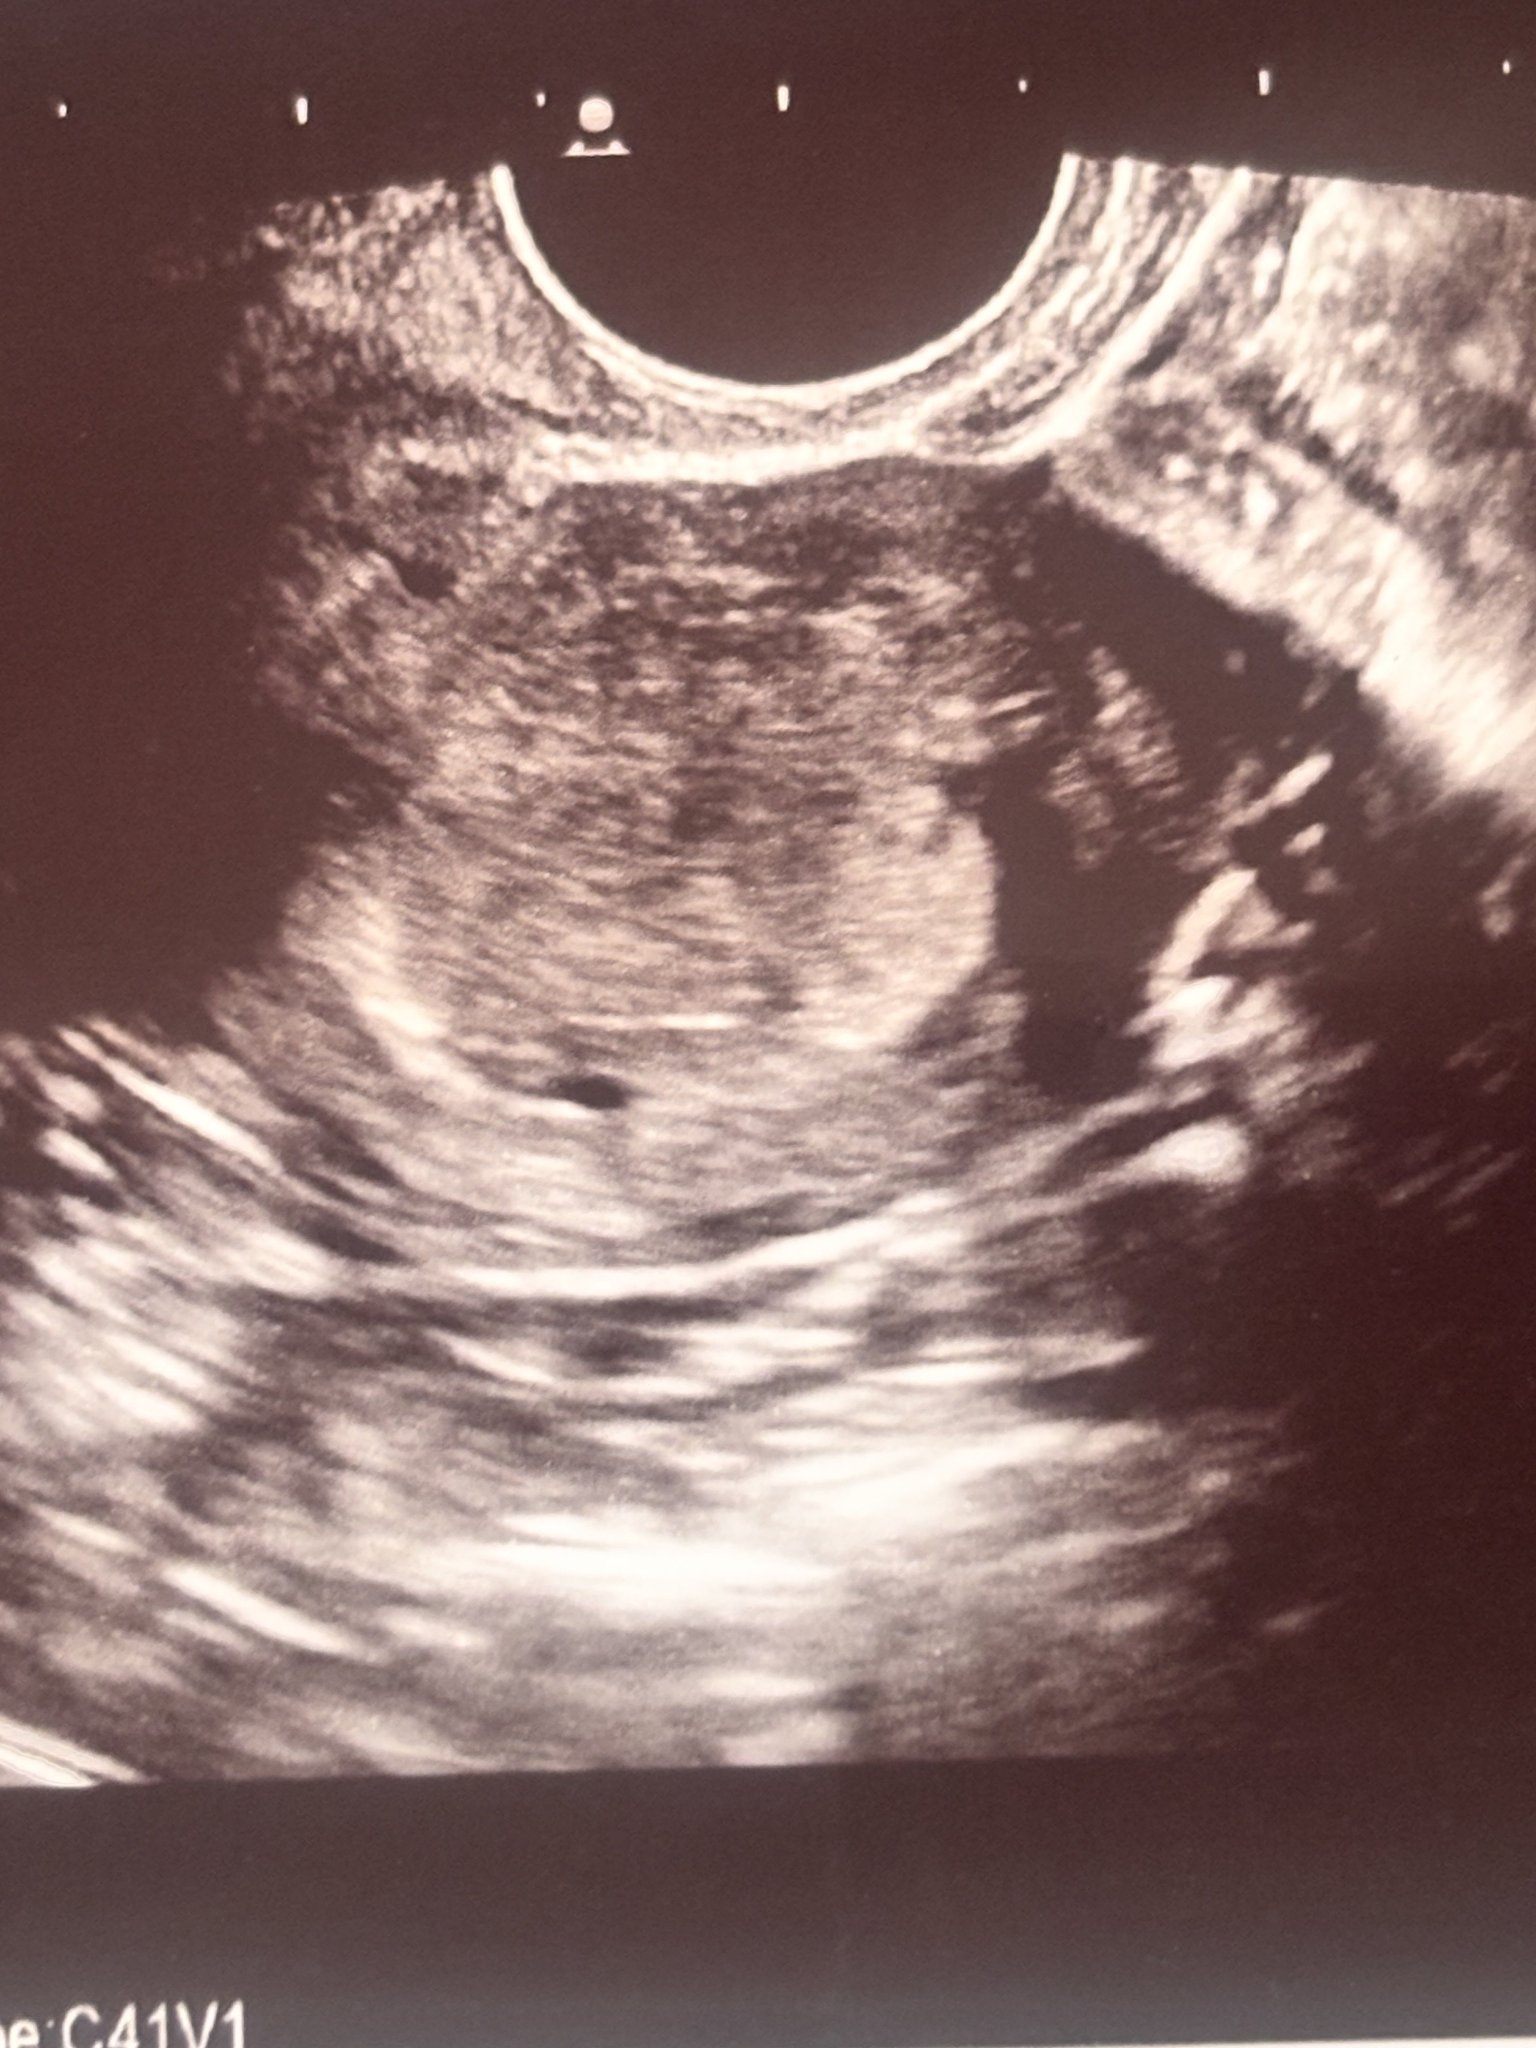

Здравейте, момичета! Имам нужда от вашата помощ. Днес бях на преглед за потвърждение на бременност, потвърдена е... Но доктора беше изключително груб, не ме гледа вагинално, само коремно, не ми каза в коя седмица съм. Каза че не вижда ембрион, а на мен сякаш ми се вижда. Последния цикъл ми беше на 28 август. Моля, дайте вашето мнение относно седмиците и снимката.

Мен докторката въобще не ме е гледала с вагинален ехограф също, нямам идея защо, но в същата седмица при мен се видя абсолютно същото, малко сакче с жълтъчно мехурче. Седмица по-късно пак с коремен ехограф видяхме ембриончето и сърдечната дейност. Не ви е казала размери, защото на този етап, мерено с коремен ехограф нищо няма да излезе. Това, което виждаш не е ембрион, много е рано да се види, това което може би виждаш е жълтъчно мехурче.

На тази снимка виждате ли сак? АГ не беше много сигурна и малко ме притесни. Трябва да съм в 5гс.

Ами прилича на сакче, раничко е, отидете към 7г.с, тогава ще се види и сакче и ембрионче, и сърдечна дейност дори. Разбира се, ако има бременност.

Доктора каза че още е рано и каза че това може би е сак.Вие как мислите?